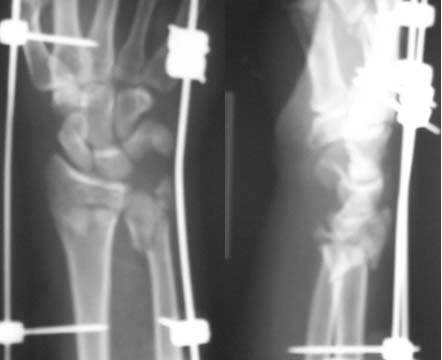

Thank you all for the encouraging participation in discussing this case. This is what I have done: I had doubt on the carpal bone involvement and a 3DCT scanwas done and this ruled it out. Patient was immediately taken up and a closed manipulation with ligamentotaxis using JESS/ UMEX (I really do not know the difference between the two, advantages / disadvantages except that UMEX is slightly coslty) under image intensifier was done. The picture is attched for your viewing. Subsequently I have added two diagonal connecting rods between the two sides to add stability. Lots and lots of elevation, mobilisation of fingers, elbow and shoulder etc done. The numbness in the median nerve area has improved significantly. This week it will be three weeks and the swelling is settled to a large extent. I am planning an elective cancellous bone grafting to the comminuted area with additional K wires as suggested by many list members and my colleagues. Would welcome further comments.